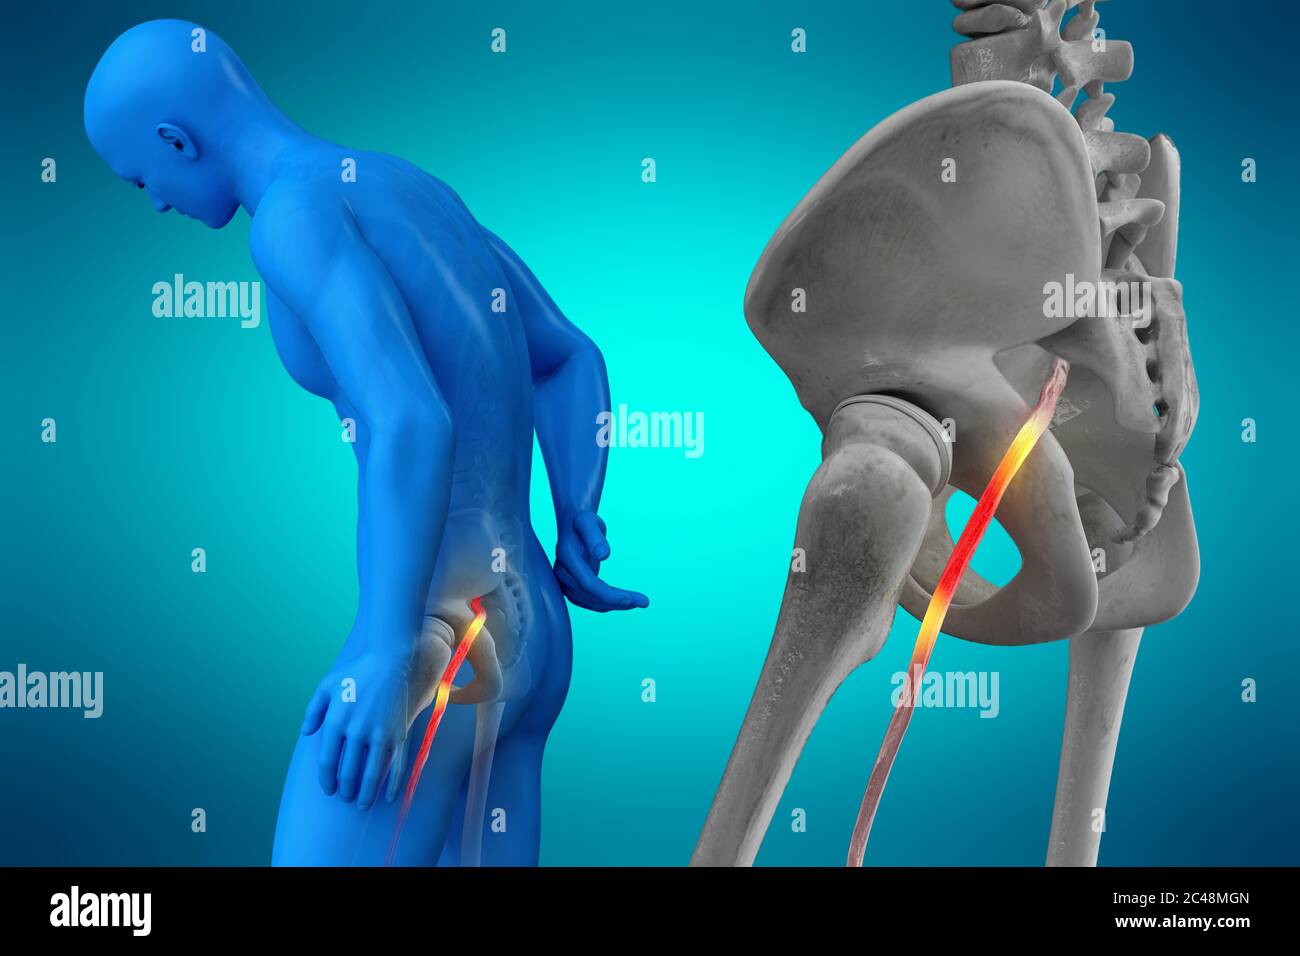

Nerf sciatique humain pincé, vision anatomique. illustration 3d. Banque D'Imageshttps://www.alamyimages.fr/image-license-details/?v=1https://www.alamyimages.fr/nerf-sciatique-humain-pince-vision-anatomique-illustration-3d-image364068117.html

Nerf sciatique humain pincé, vision anatomique. illustration 3d. Banque D'Imageshttps://www.alamyimages.fr/image-license-details/?v=1https://www.alamyimages.fr/nerf-sciatique-humain-pince-vision-anatomique-illustration-3d-image364068117.htmlRF2C48MGN–Nerf sciatique humain pincé, vision anatomique. illustration 3d.